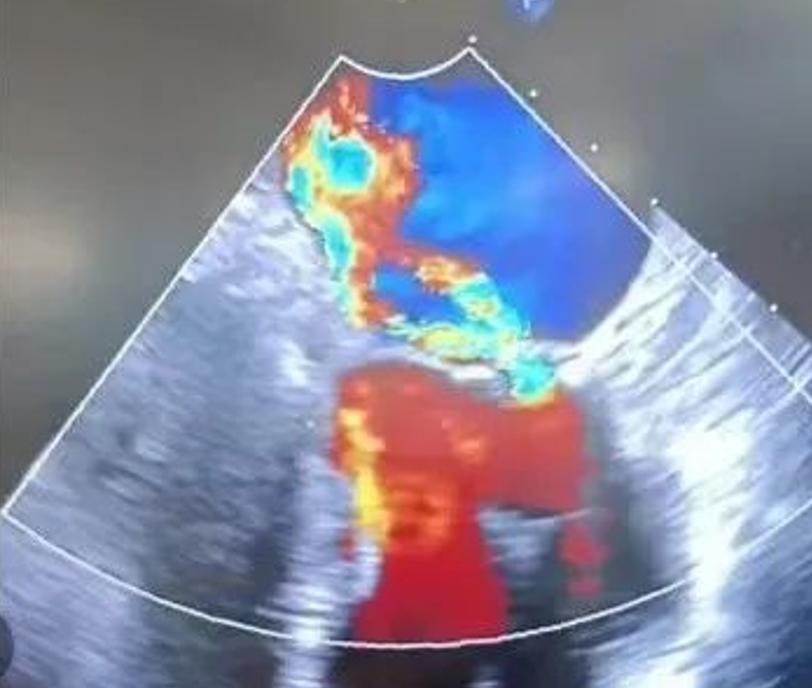

到了 2023 年,患者开始出现房性心律失常以及活动后胸闷气短,复查心脏彩超发现二尖瓣已经重度返流,并且有一个瓣膜出现了脱垂的情况。

术前心脏彩超

再通过三维食道超声进行精准全方位判断:夹闭稳固;位置合适;没有造成狭窄;没有影响其他结构;夹闭后返流明显减轻。